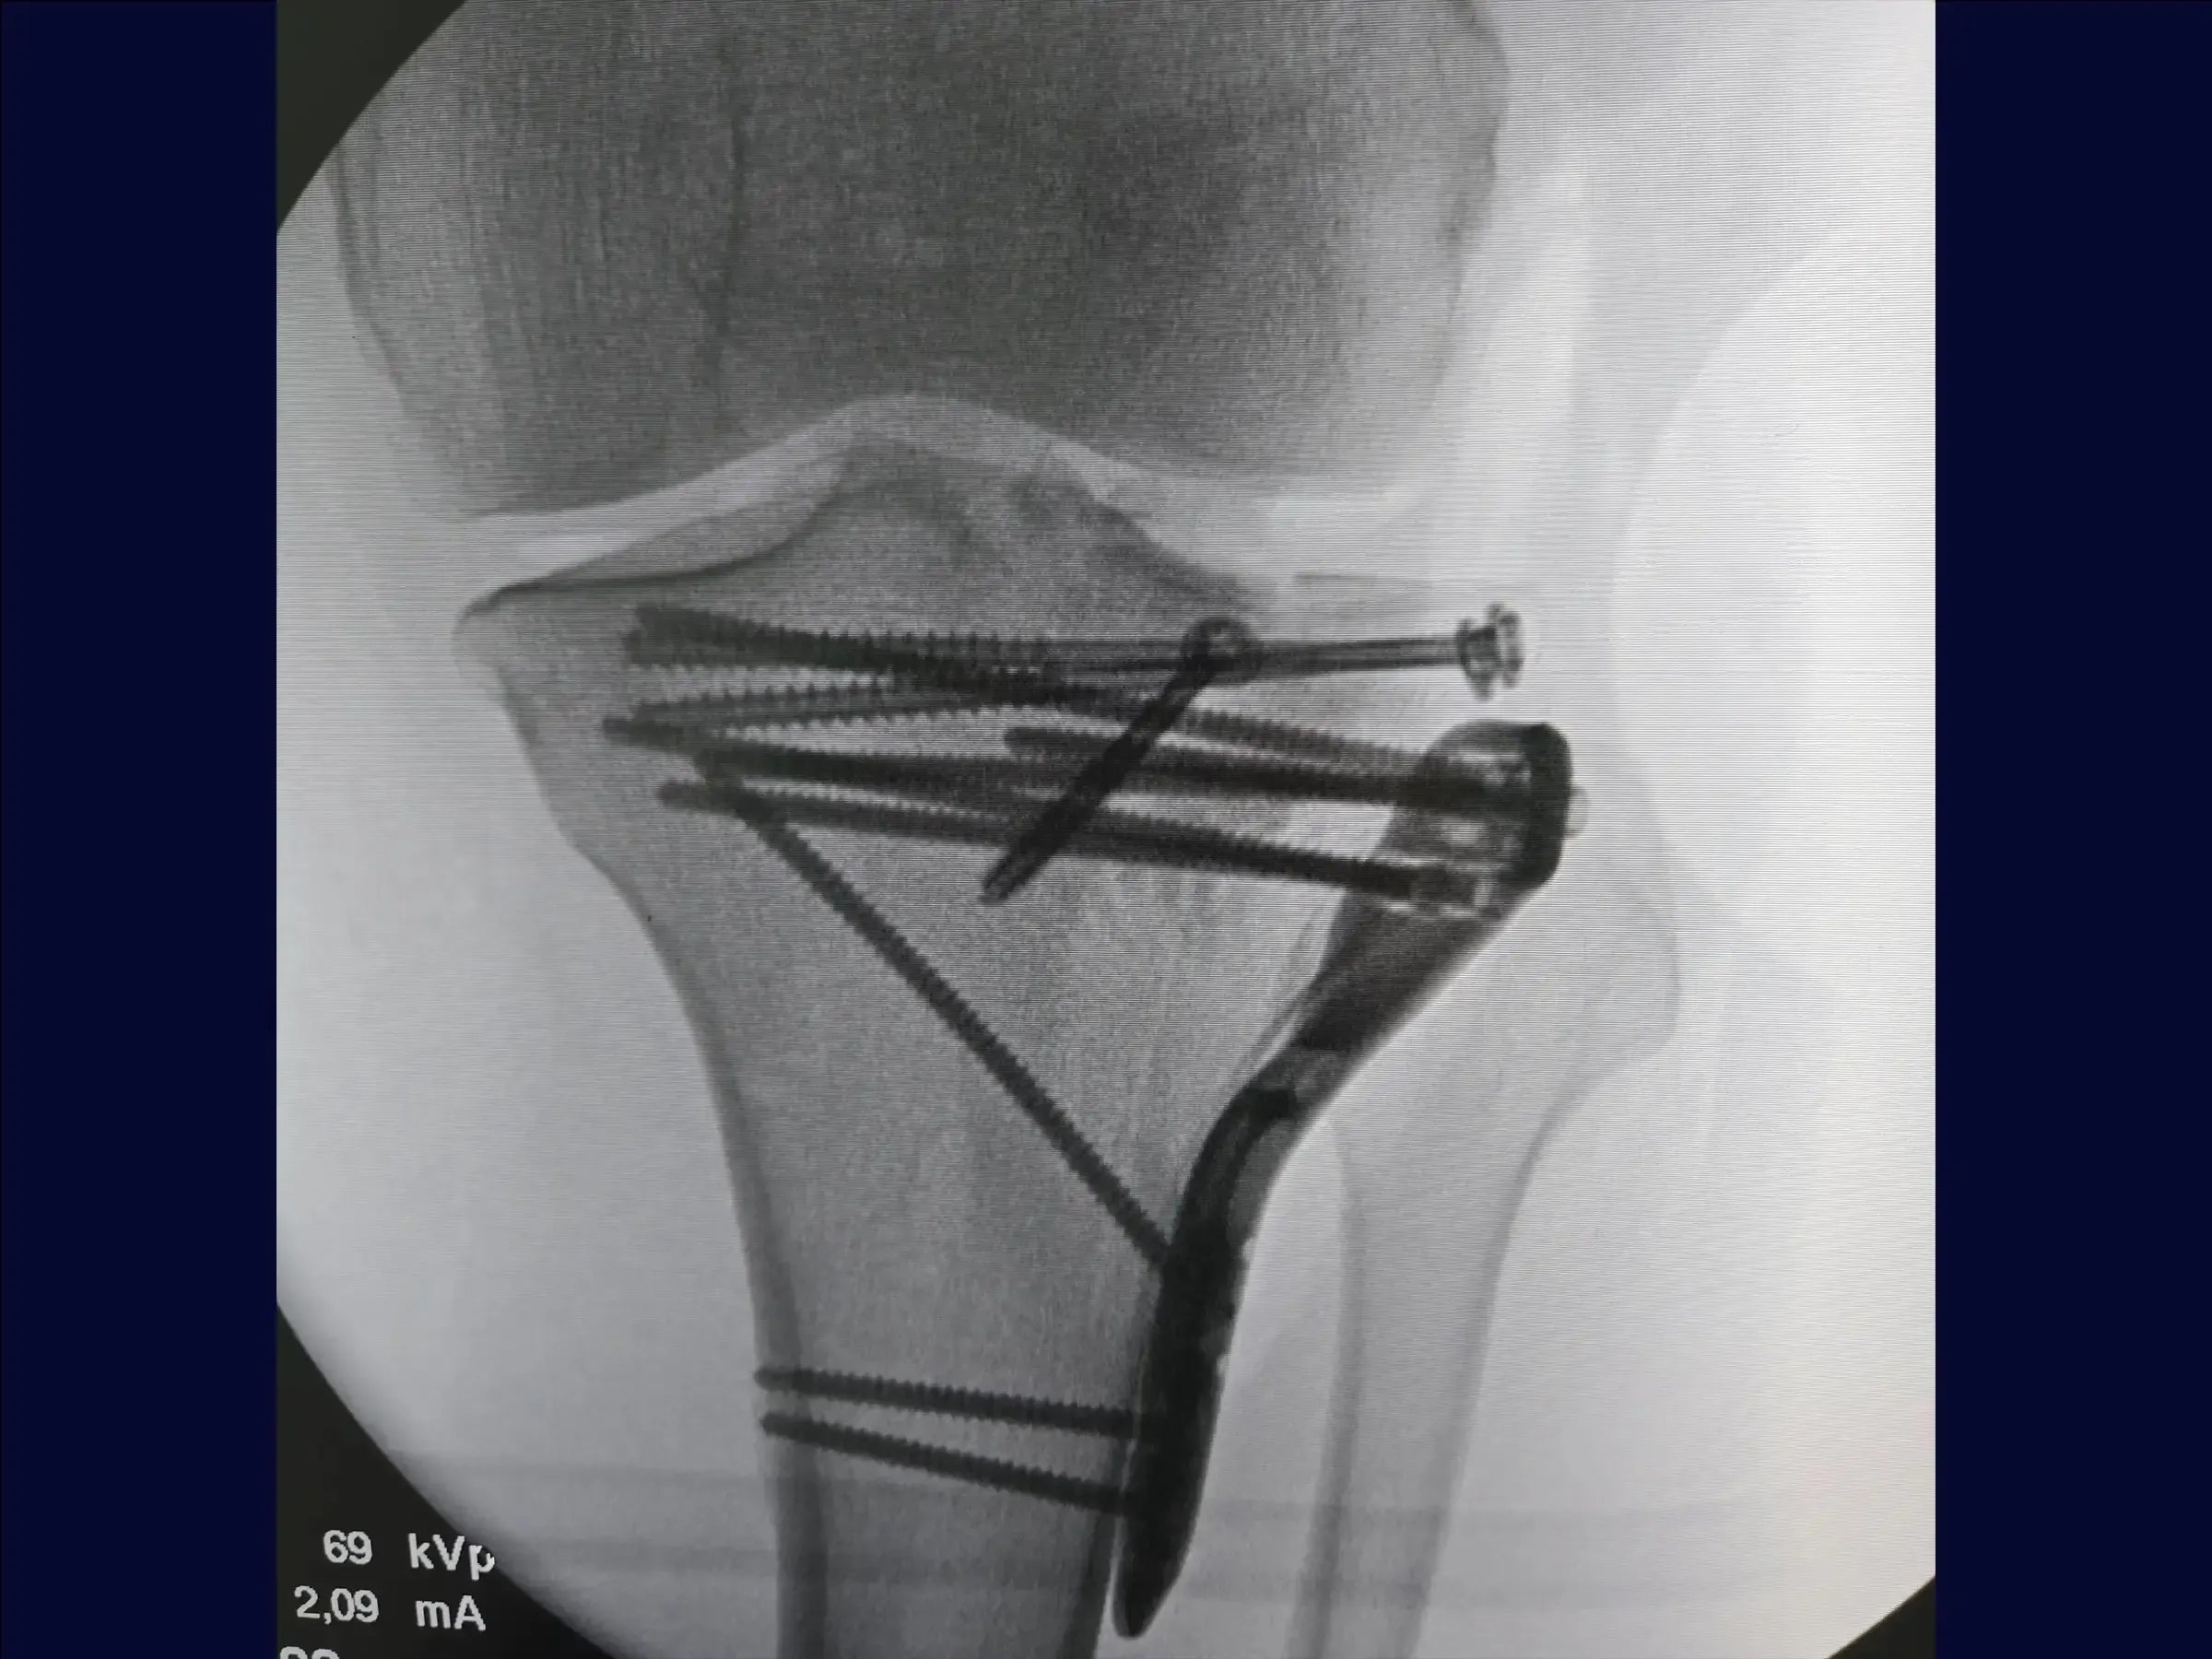

- Utilização de enxerto ósseo estrutural e fixação com parafusos canulados subcondrais e placa.

- Fixação Estável e Rede Subcondral: Posicionamento de fios guia para parafusos canulados subcondrais, criando uma "rede" para estabilidade primária, e utilização estratégica da placa para compressão e manutenção do levantamento.

- PDF Detalhado: Resumo prático do procedimento, abordando: condição da fratura (platô tibial com afundamento central e cisalhamento incompleto); acesso cirúrgico anterolateral em "taco de hóquei"; preparação e dissecção detalhada; manuseio do menisco e osteotomia incompleta (elástica); levantamento da depressão e enxertia; fixação com parafusos canulados e placa; e fechamento por planos para restauração anatômica e tecidual, culminando em redução anatômica e boa estabilização.